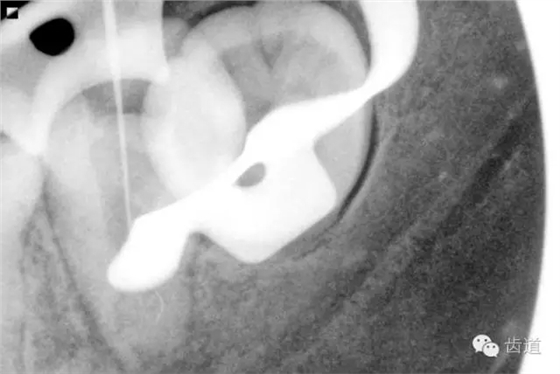

2. 術(shù)前X片

可見(jiàn)37根管影像清晰,根中上三分之二粗大,根尖三分一分為近遠(yuǎn)中兩根管,形態(tài)均呈弧形,根尖周膜連續(xù)性中斷,根尖周透射影明顯